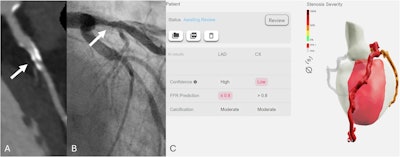

False-positive case. A representative case of an 81-year-old male patient with a recent onset of stable chest pain. Curved multiplanar reconstruction coronary computed tomography angiography (A) shows a heavily calcified plaque with blooming artifacts (white arrow) in the proximal left anterior descending artery with obstructive stenosis. Invasive coronary angiography (B) demonstrates a 26%-50% stenosis, and Fractional Flow Reserve was 0.89, in contrast to the report of CT-FFRAI that predicts FFR ≤ 0.8 (C). Of note, the patient also had an obstructive stenosis on the left circumflex artery with CT-FFRAI > 0.8 prediction and invasive Fractional Flow Reserve > 0.8 (FFR = 0.91).Peters et al; European Radiology